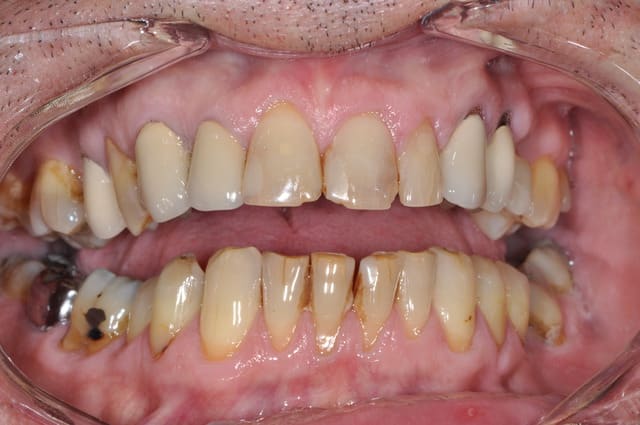

22 21 et 11 ce sont des indications de facettes, pourquoi mutiler complètement la dent ?

4 facettes.

les couronnes dans la foulée ou +tard suivant ses moyens et envies.

Pour la 22 qui est intacte, pourquoi pas. Pour les deux autres, à partir du moment où on a un composite proximal qui va également sur la face palatine, j'estime que la couronne est mieux indiquée. Le jour où on aura une infiltration, on sera bien embêté. Pourquoi s'empêcher de soigner totalement quelqu'un sous des prétextes intellectuels.

Vous me faites marrer avec vos notions de mutilation : quand ça vous arrange de le dire, il y a mutilation, et pas de mutilation quand ça ne vous arrange pas (cf le cas de tétracycline que tu voulais traiter par facettes : si c'est pas de la mutilation, c'est quoi ?)

faut lui proposer la 14.....pour les facettes je ne suis pas pour , cela ne cadre pas avec ce type de patients (hygiène pas top)...comment est il , penses tu pouvoir obtenir qu'il passe des brossettes interdentaires , qu'il n'ai plus de brossage iatrogène ....

hum.........c'est une joke mais assure toi de sa motivation à changer de type d'hygiène et financière avant de te lancer dans un travail esthétique pur (facettes.....)

Le cas de tetracycline c'est abstention ou facette, si tu veux un résultat esthétique c'est facette... la mutilation commence dés qu'on prend notre fraise... le tout c'est de mutiler le moins possible... chaque tissu conserver est un plus pour le pronostique de la dent, si tu as pas compris ça moi tu me fais pas rire ... (mode Apap On)